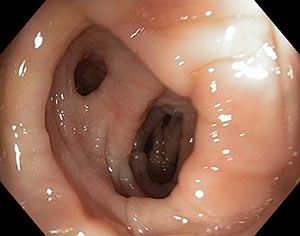

Sono delle piccole estroflessioni della parete dell’intestino, più spesso nel colon sinistro e nel sigma, in soggetti predisposti e sofferenti di stitichezza.

La presenza di diverticoli del colon (diverticolosi) di per se non causa alcun disturbo. L'infiammazione dei diverticoli ( diverticolite) che può essere causa di ulcerazione, sanguinamento e perforazione.

Colonscopia ( sconsigliato nella fase acuta della diverticolite)